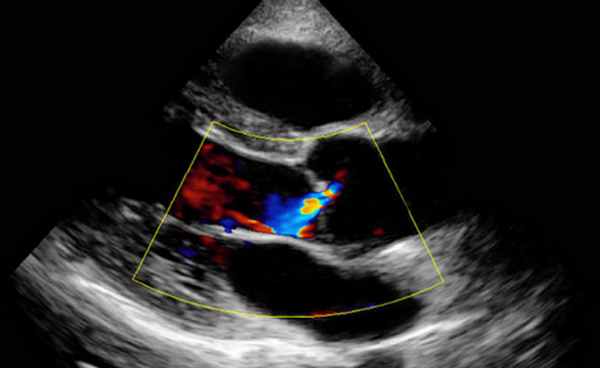

Метод РНТ — самый простой, но менее надежный для применения сразу после баллонной ангиопластики у больных с тяжелой АР или высоким давлением наполнения. Этот метод недооценивает тяжесть стеноза МК в этих ситуациях, поскольку укорачивается РНТ. Уравнение непрерывности нельзя использовать при выраженных АР или MP. На метод PISA не влияет наличие других пороков. ЭхоКГ-признаками тяжелого стеноза МК являются:

1) средний ДР в покое > 10 мм рт. ст.;

2) площадь отверстия МК < 1 см2;

3) РНТ > 220 мсек.

Целесообразно выполнить ДЭхоКГ-исследование гемодинамики во время велоэргомефии, после тредмил-теста или во время введения добутамина больным с клинической симптоматикой, у которых недостаточно данных для диагностики тяжелого стеноза МК. При физической нагрузке значимо увеличивается трансмитральный Р в ЛП и ЛА за счет роста СВ и ЧСС. Средний Р > 15 мм рт. ст. при нагрузке свидетельствует о наличии тяжелого митрального стеноза. Средний ДР на МК > 18 мм рт. ст. при введении добутамина прогнозирует клинические события с точностью до 90%. У больных с митральным стенозом выраженность симптомов больше всего коррелирует со степенью ЛГ. Это относится и к больным, принимающим бета-АВ для снижения ЧСС в ответ па нагрузку или перенесшим митральную комиссуротомию.